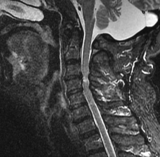

65岁的杨大爷,近半年来总觉得身体有些“不对劲”。先是双手指端常常发麻,拿筷子、扣扣子这些以前轻而易举的小事,现在做起来却有些笨拙乏力。慢慢地,双腿也像是灌了铅,走路发飘,深一脚浅一脚,用他自己的话说:“像踩在棉花上,总感觉要摔倒。”和许多同龄人一样,杨大爷最初把这一切归咎于“年纪大了,机器零件老化了”。他想着,人老了,行动不利索是正常的。然而,症状并没有因为他的“想当然”而好转,反而日益加...

文章附图

颅颈连接处包括枕骨、寰椎和轴椎。这一狭小区域创伤,导致不稳定、畸形、压迫神经根、脊髓,受伤时常发生突然死亡,幸存者由于颈椎不稳定,也会极度疼痛或延迟性猝死。非创伤性病变(如肿瘤)进展为脊髓神经功能障碍、极度疼痛,最终死亡。目前,缺乏对上颈椎...